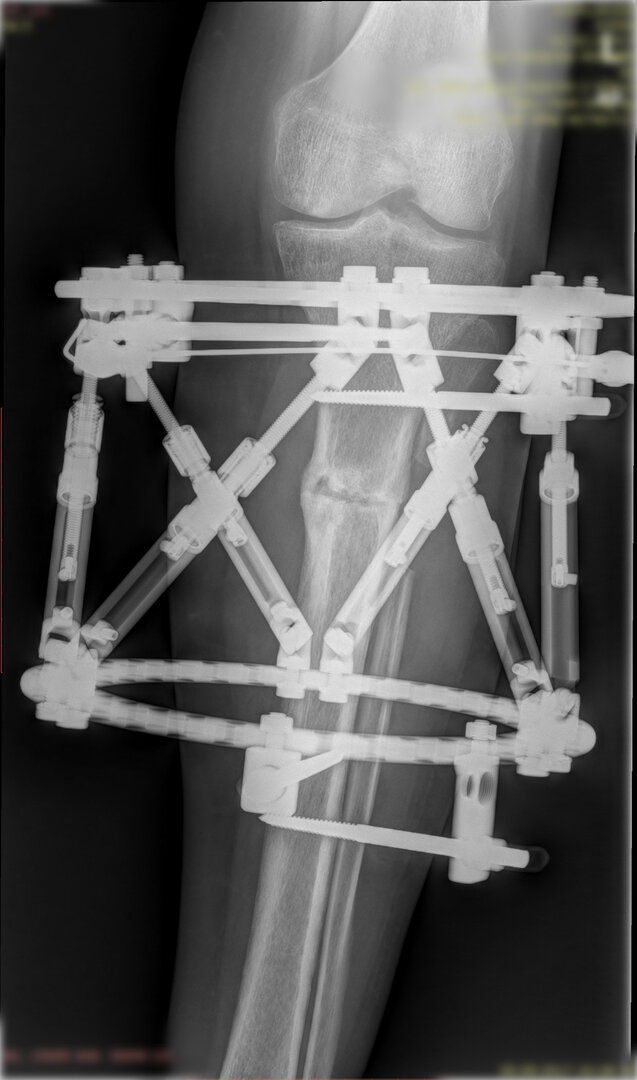

Deformitenin yeri ve miktarına bağlı olarak bilgisayar destekli sirküler eksternal fiksatör ile tedrici düzeltme yapılabilir. Bu sistemin avantajı düzeltme esnasında sistemle oynayarak yeni düzenlemeler yapmanıza izin vermesidir.

Bu ameliyat öncesi bir deformite analizi yapılıp hangi kemikte, normalden ne kadar sapma olduğu tespit edilir. Daha sonra bu kemiğe yine ostetomi yapılarak bu anormal sapma düzeltilir.  Bu düzeltme plak-vida veya intramedüller çivi ile akut olarak düzeltilebileceği gibi bilgisayar destekli sirküler eksternal fiksatör ile tedrici olarak ta yapılabilir. Hangi yöntemin hangi hasta için uygun olacağına hasta özelinde karar veriyoruz, ne tür cerrahi tedavi olması gerektiğini danışabilirsiniz.